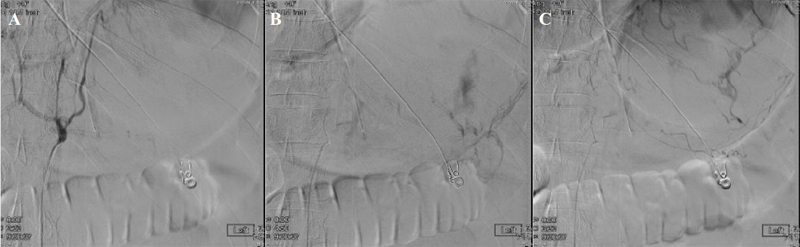

Figure 2. (A–C) Fluoroscopy-guided embolization of the gastroduodenal artery using 500–700-micron particles. The procedure was partially successful but did not fully control the bleeding.

Despite initial control, the patient experienced recurrent hematemesis with his hemoglobin decreasing from 13.4 g/dL to 8.0 g/dL. Epinephrine was administered locally, but no active bleeding was identified. With worsening hemodynamic instability, interventional radiology was consulted, and a CT with angiography was performed. The angiogram showed no active GI bleed but did reveal a large intragastric blood clot (12 cm). The patient was transferred to the ICU after a 30-hour bleeding-free interval, and interventional radiology performed an empiric embolization of the gastroduodenal artery using 500–700-micron particles. However, this failed to achieve adequate control of the bleeding (Figure 2).